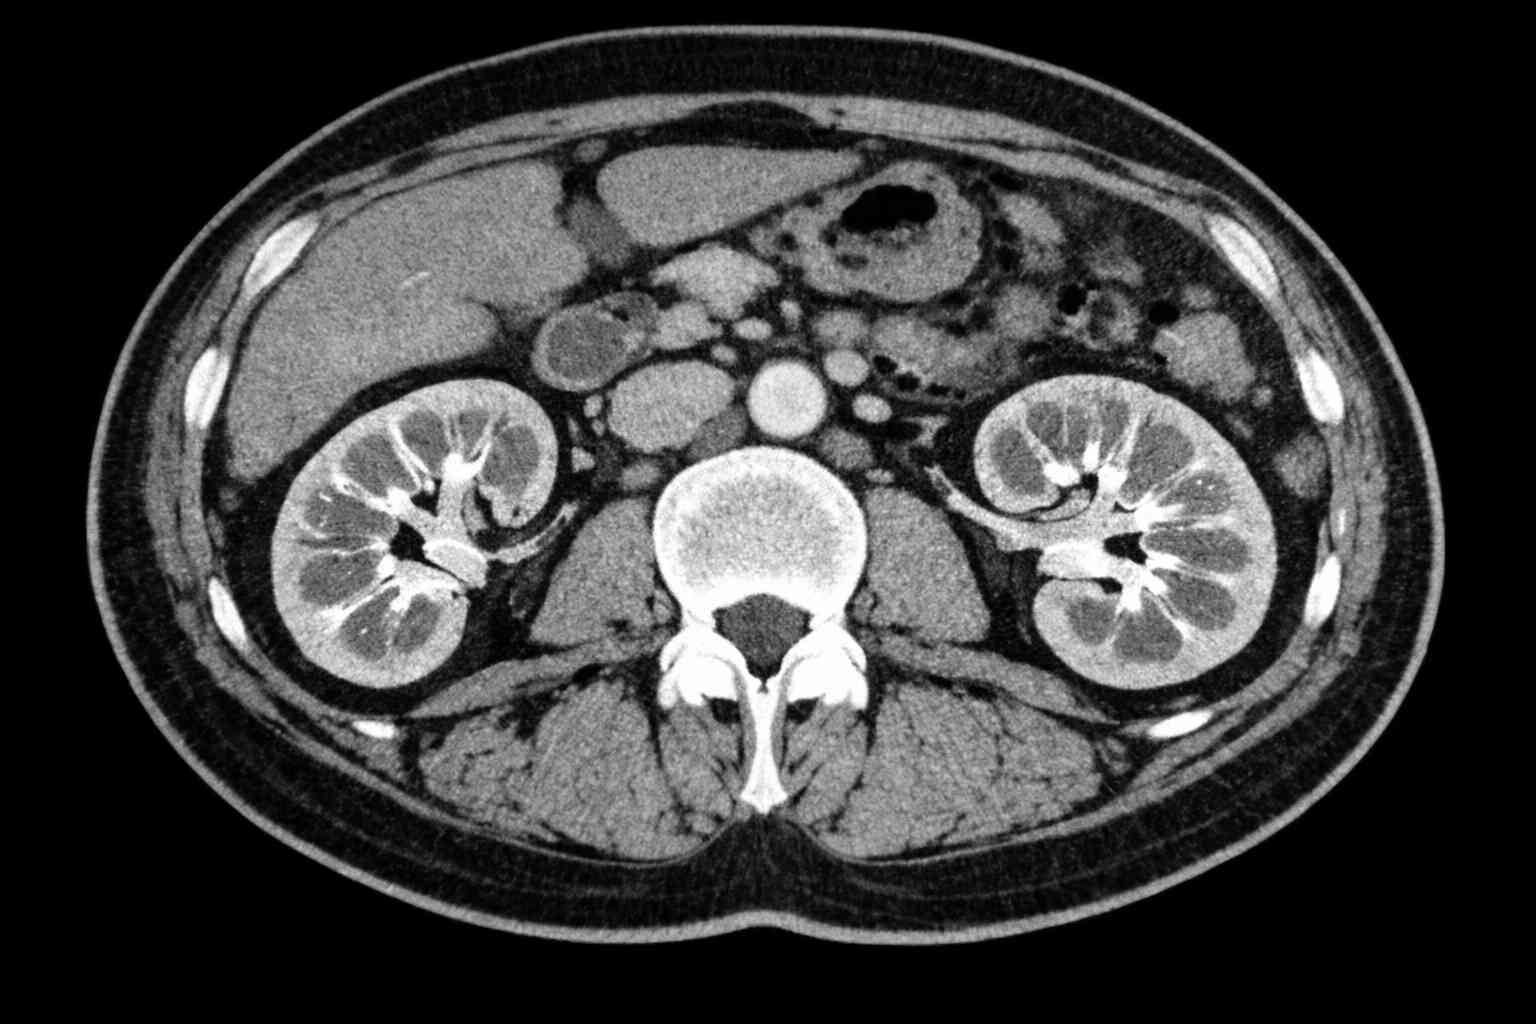

Νεφροκυτταρικός καρκίνος: Νέο κεφάλαιο στη στοχευμένη θεραπεία

Ο προχωρημένος νεφροκυτταρικός καρκίνος (advanced renal cell carcinoma – aRCC) αποτελεί μία ετερογενή νόσο με σύνθετη βιολογική συμπεριφορά και συχνά απρόβλεπτη κλινική πορεία. Τα τελευταία 15 χρόνια, το θεραπευτικό τοπίο έχει αλλάξει ριζικά χάρη στην ανάπτυξη στοχευμένων θεραπειών και ανοσοθεραπευτικών…